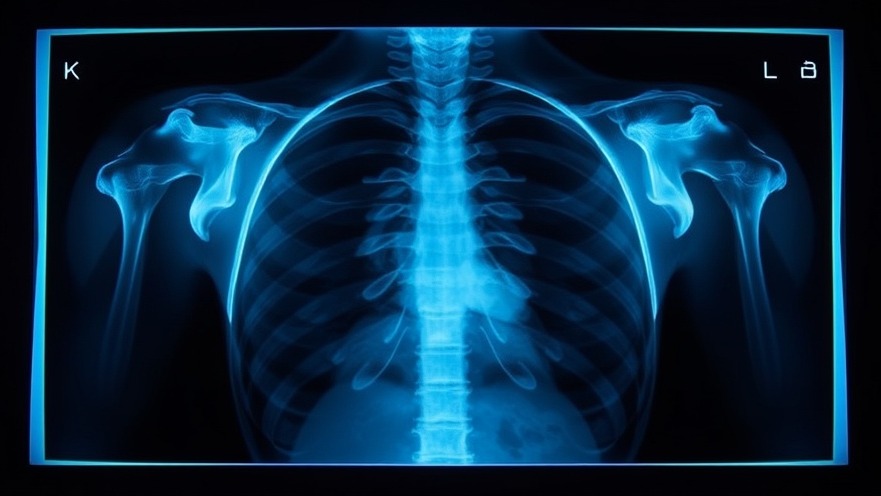

Medical x-rays have become a cornerstone of modern healthcare, providing critical insights into patients' health conditions. As digital nomads navigate their health while abroad, understanding how x-rays work and their importance becomes essential. These imaging procedures not only help in identifying injuries like broken bones but also play a vital role in detecting life-threatening illnesses.

Understanding Radiation Exposure from X-Rays

Despite the common use of x-rays, many individuals have concerns about the radiation exposure associated with these medical procedures. In fact, according to the CDC, medical x-rays typically involve lower doses of radiation compared to other imaging techniques such as CT scans. For the average American, medical x-rays are the most significant source of man-made radiation exposure. However, it’s crucial to weigh the benefits against the risks—what is learned from an x-ray should justify the exposure.